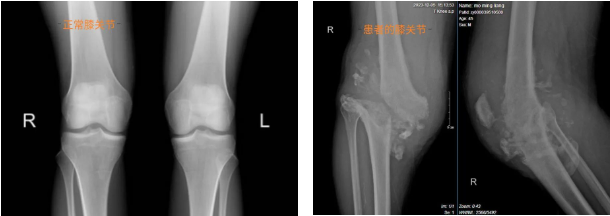

经过完善相关检查,最终被诊断为“夏科氏关节病”。关节、运动医学科主任吴毅华主任医师带领科室医疗团队再次对该患者进行认真问诊和检查,发现患者右膝关节明显肿胀,右下肢与左下肢不等长,相差达5cm,活动时存在关节错位、弹响,并伴有软组织不平衡、骨缺损等问题。这是一种罕见的骨科疾病,对该类患者行关节置换,是关节外科技术的一道“难题”,国内外鲜有报道,并且该患者情况更为复杂,如果用普通的膝关节假体行膝关节置换,术后可能出现膝关节不稳定而影响膝关节的活动功能的问题,因此普通的膝关节假体不能满足其需求。

患者术前膝关节图片

膝关节X线图片对比